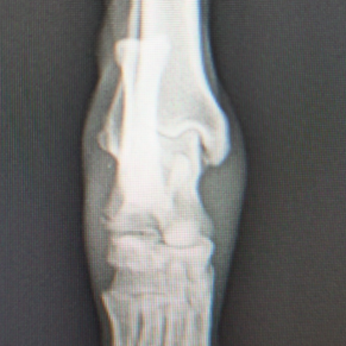

症例:柴犬 3歳

左後肢の完全挙上を主訴に来院されました。触診にて近位足根関節の過伸展を、レントゲン検査にて左足根関節周囲の軟部組織の腫脹、ストレス撮影によって距骨・踵骨と第4足根骨・中心足根骨間の脱臼および過伸展を認めました。

術前正面像左関節の腫れ

左足根関節の軟部組織が腫脹しています。

術前正面像

術前側面像屈曲位